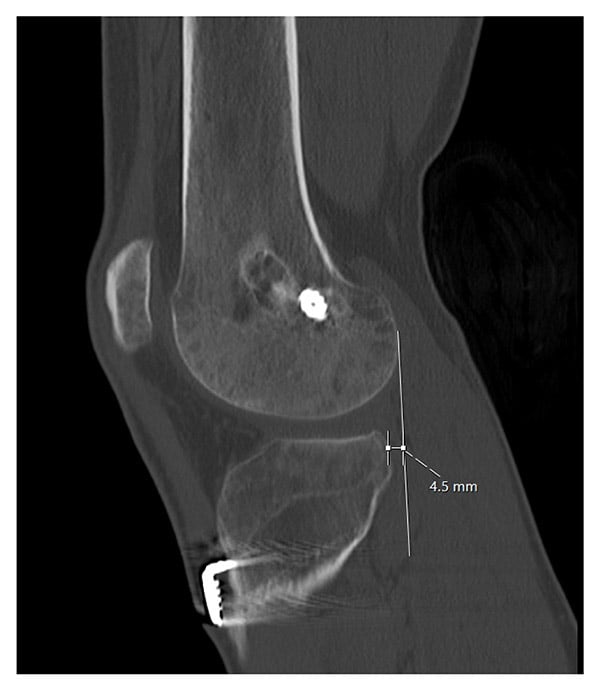

The patient underwent anterior closing wedge high tibial osteotomy with medial meniscus repair, hardware removal, and bone grafting of the prior ACL tunnels. Six months later, he underwent hardware removal, revision ACL reconstruction, and lateral extra-articular iliotibial band tenodesis. The latter was indicated given the multiple failures of prior ACL reconstructions, along with high-grade laxity (grade-3B Lachman, grade-3 pivot shift). His final physical examination demonstrated a 1A Lachman, no pivot shift, and stable collateral ligaments. There was full extension without hyperextension, and he flexed to 135°. The tibial subluxation had resolved, and the posterior slope was reduced to 4° (Figures 3 and 4). He returned to an active lifestyle but was counselled against returning to high-pivoting sports, given his extensive history of instability.

Figure 3: Postoperative right knee computed tomographic scan after ACWO but before revision ACL reconstruction shows reduced anterior tibial subluxation of 4.5 mm.